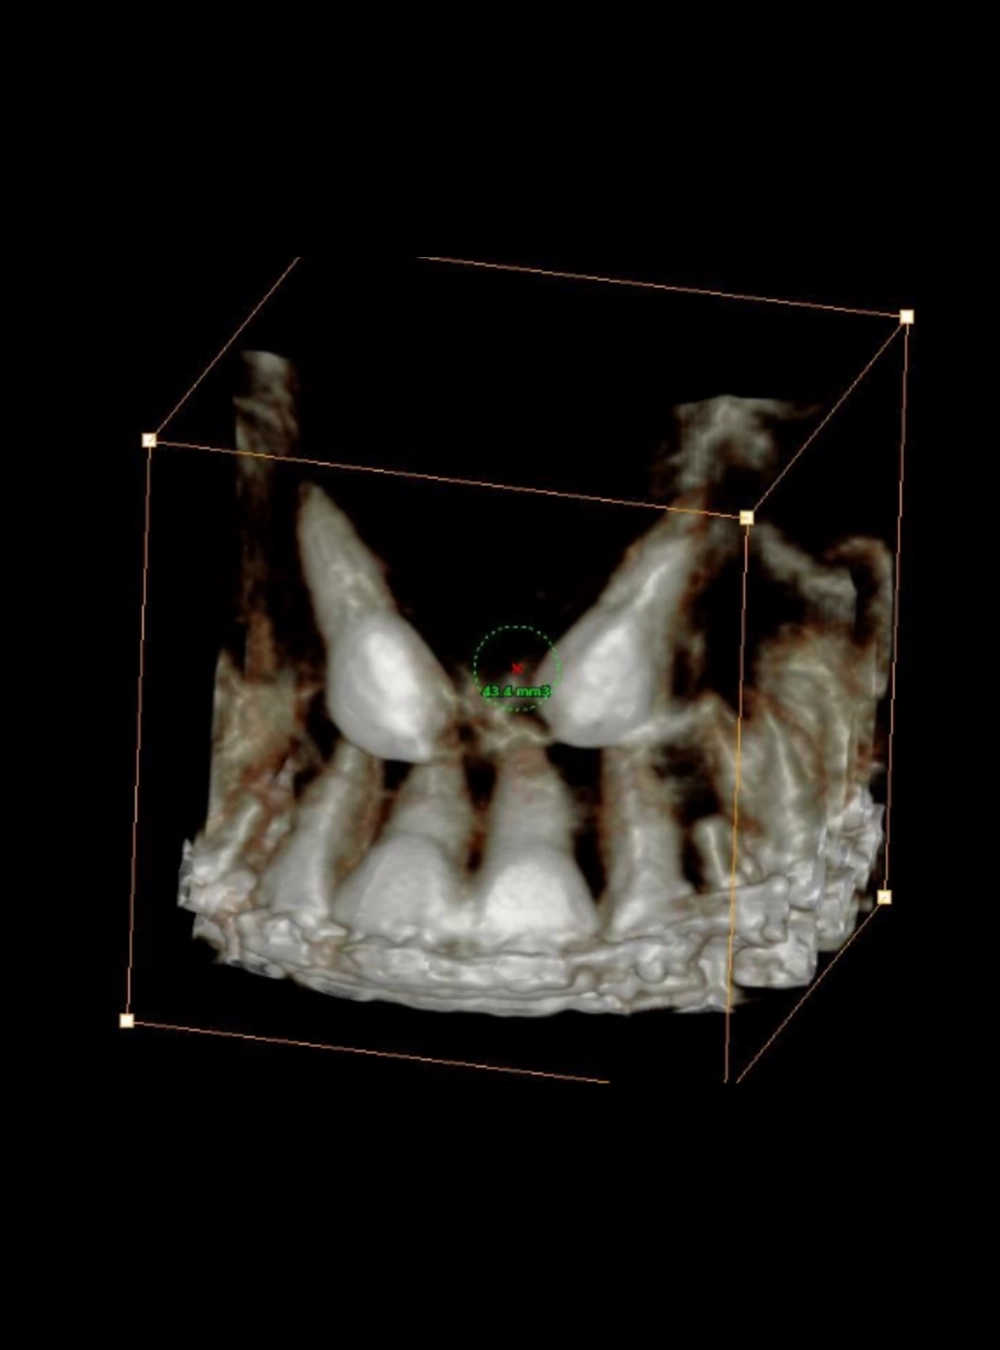

Dientes Retenidos - Vista RX

Dientes retenidos - Vista Tomografía

Estudios 3D

• Tomografía Completa Cone Beam

• Tomografía Endoscan 5x5

• Tomografía Ambos Maxilares (Implantes)